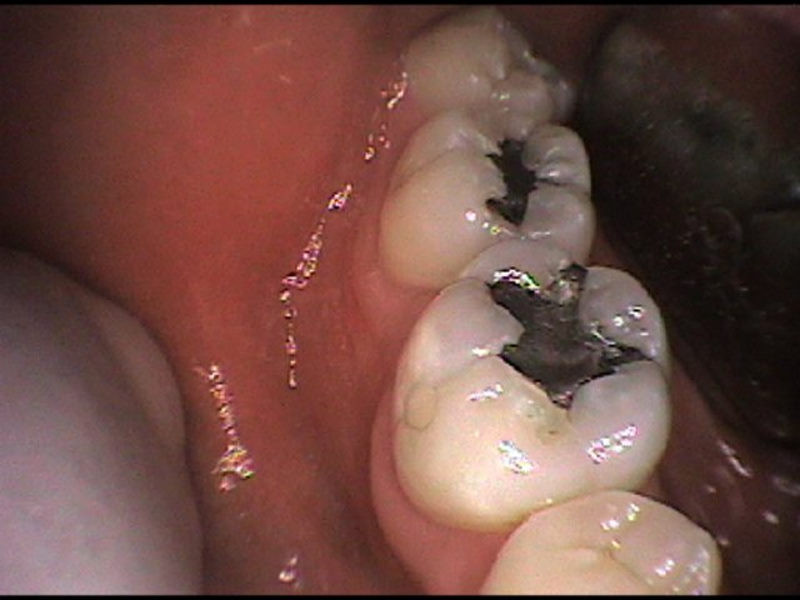

Cambio de amalgama a restauración estética

Envíado por Grupo Dental de El Salvador